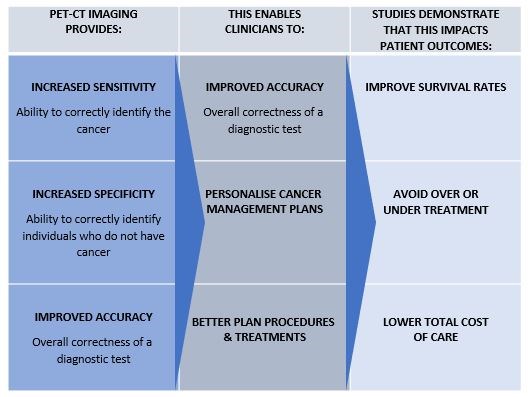

PET-CT provides oncologists with accurate information on the extent and severity of disease which enables them to better plan a patients cancer management and treatment, avoiding over or undertreatment, and potentially improving patient outcomes.

What are the benefits of a PET-CT scan?